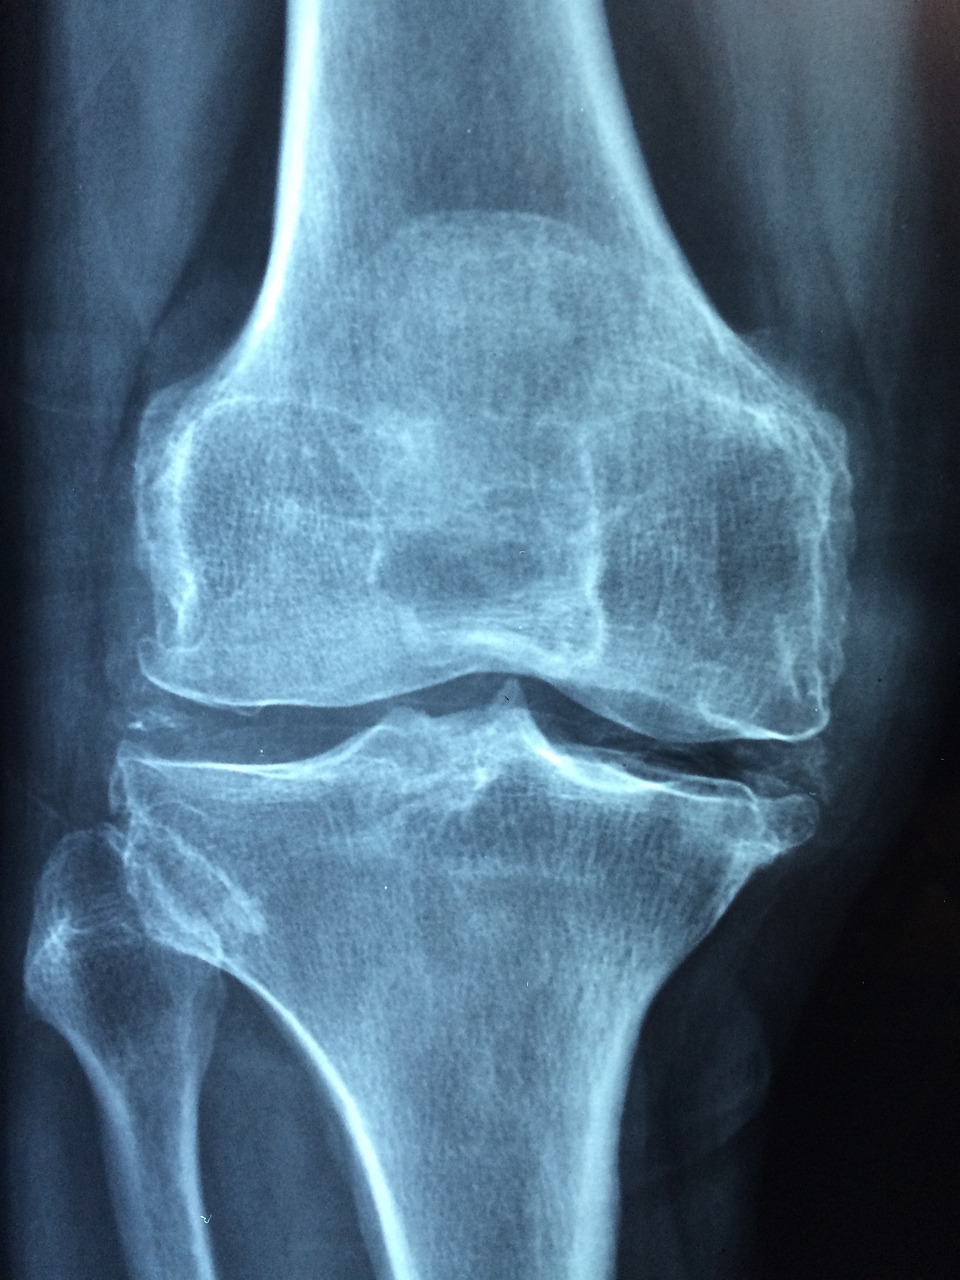

▶ 칼슘 + 비타민D + 마그네슘 - 골다공증 예방 & 관절 건강 유지

50대 이후에는 골밀도 감소 속도가 더욱 빨라져 골절 위험이 높아지므로, 칼슘·비타민 D·마그네슘을 함께 섭취해야 합니다.

✔ 골다공증 예방 & 뼈 건강 유지

✔ 관절 건강 보호 & 근육 경련 예방

✔ 면역력 강화 & 신경 안정 효과💡 추천 대상

👉 골밀도가 감소하여 뼈 건강이 걱정되는 여성

👉 근육 경련이나 허리·무릎 통증이 있는 경우💊 섭취법

– 칼슘 1000mg + 비타민 D 5000IU + 마그네슘 300~400mg📌 TIP

👉 비타민 K2와 함께 섭취하면 칼슘이 뼈로 흡수되는 효과 상승!

▶ 글루코사민 + MSM - 관절 보호 & 연골 강화

50대 이후에는 연골이 닳고 관절이 약해지면서 무릎 통증이나 손가락 관절 통증이 증가할 수 있습니다. 글루코사민과 MSM은 연골을 보호하고 관절의 염증을 완화하는 데 도움이 됩니다.

✔ 관절 건강 보호 & 연골 손상 예방

✔ 관절 염증 완화 & 통증 감소

✔ 연골 생성 촉진 & 유연성 증가💡 추천 대상:

👉 무릎이나 손가락 관절이 불편한 여성

👉 오래 서 있거나 걷는 일이 많은 경우💊 섭취법:

– 글루코사민 1500mg + MSM 1000mg📌 TIP:

👉 비타민 C와 함께 섭취하면 연골 재생 효과 상승!